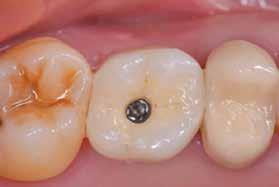

Egy fiatal páciens jelentkezett nálunk, akinek eltörött a szabad véggel rendelkező hídja (1. ábra). A hiányzó, első premoláris fog esetén implantációs pótlást javasoltunk. A csontállomány értékeléséhez CBCT-vizsgálatot végeztünk, és az elemzéséhez NNT Viewert (NewTom) használtunk, és copaSKY 4×10 mm-es (bredent medical) implantátumot választottuk a fog pótlásához

1. ábra: Műtét előtti fogászati panorámafelvétel, amelyen a hiányzó felső állcsont jobb első premolárisát és a szabad véggel rendelkező hidat láthatjuk. — 2. ábra: Az implantátum méreteinek megtervezése CBCT-vel. 3. ábra: Bukkális lágyrészdefektus. — 4. ábra: A biológiai szélesség értékelése a vertikális lágyszövetvastagság alapján. 5. ábra: Palatinális „tekercslebeny” – Palatal roll flap. — 6. ábra: Bredent medical copaSKY 4x10 implantátumbeültetés. 7. ábra: Szubkresztális implantátumbeültetés a várható biológiai szélességnek megfelelően.